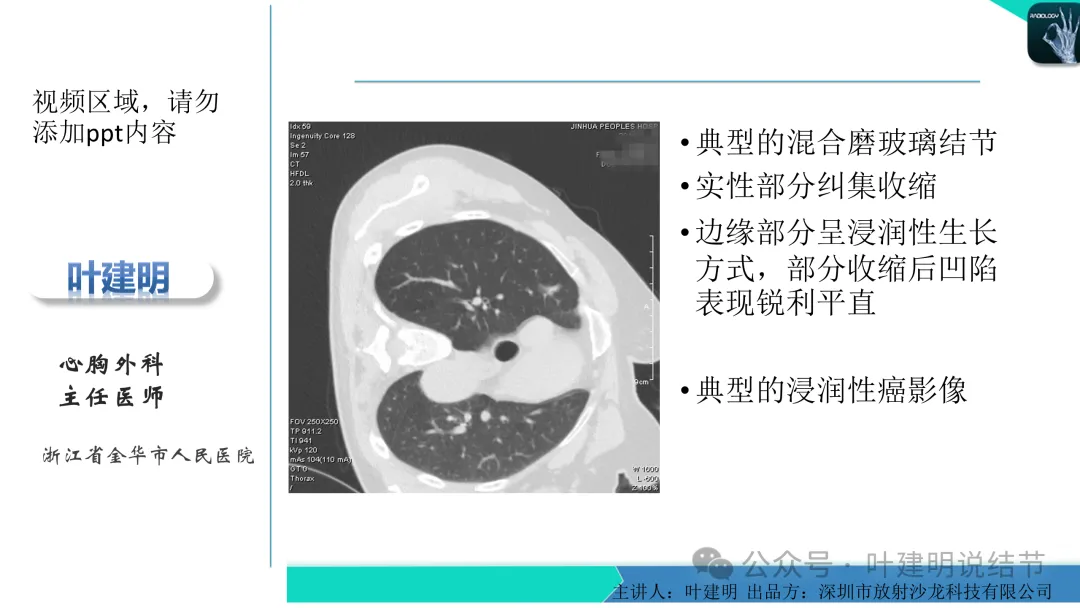

早在2020年时,我受邀在《放射沙龙》做过一个系列的精品课,当时专门总结分析过各类良恶性肺结节与肿块的影像特征,这是当时关于微浸润性腺癌影像特征的分析,今天看来仍基本不太需要改变,大家有兴趣的可以参考:

这个病灶会是微浸润性腺癌吗?当然没有病理诊断,我也不能说百分之百必不会,但这样的病灶已经风险大到必得尽快手术切除干预了吗?显然还早着呢:1、影像不是典型的结节状;2、边缘与轮廓模糊不清;3、灶内似有细支气管扩张(更容易是细支气管扩张伴少许周围炎或肺泡上皮增生);4、血管邻近走但无牵拉影响;5、没有实性成分,没有锐利毛刺,没有胸膜牵拉,没有血管进入,没有任何倾向风险性高的影像特点。我一直强调:肺结节是否要干预处理,不要纠结于最后病理是什么,而要看风险高低;而风险高低的最重要术前判断依据一是随访有无进展,二是有没有实性成分。只要没有肉眼可见的影像上的实性成分,风险就是低的!何况病理也是人看的,原位还是微浸润,不典型增生还是原位有时也在一念之间。